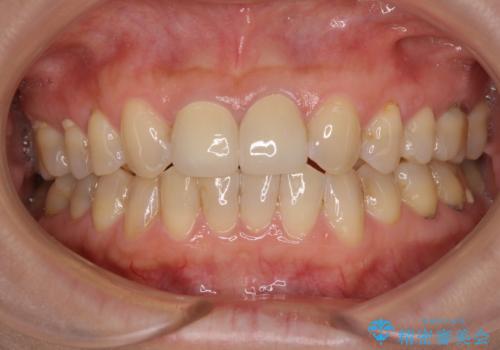

- 上顎2前歯の色を気にして来院された患者様です。

2本ともに虫歯治療による充填材の変色などによりつぎはぎのような前歯となっていたため、オールセラミッククラウンにて補綴治療を行うこととしました。

今後ホワイトニングをする予定とのことで、少し明るめのトーンに仕上げました。